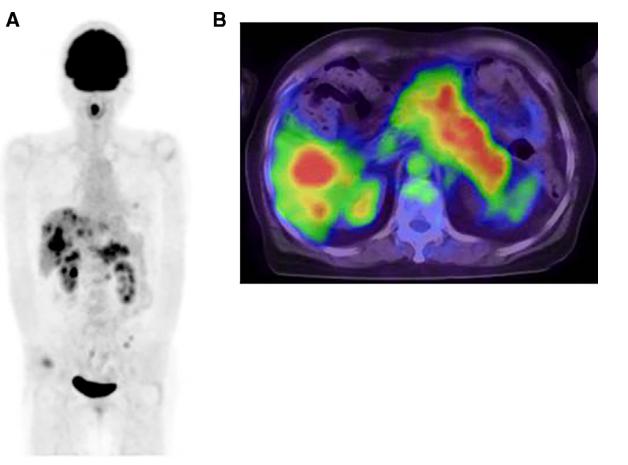

磁共振成像(MRI)显示舌内肌内1.5×2.3×2.0cm的肿瘤。肿瘤在T1加权像上呈低信号,在T2加权像上呈非均匀高信号(图2)。PET/CT发现舌肿瘤;胰腺体肿瘤从脾静脉侵犯到前面肾旁间隙;多发性肝肿瘤;肺肿瘤;盆腔内的腹膜肿块被认为是播散性的(图3A和B)。CT增强扫描显示胰体肿瘤广泛侵犯脾窦静脉至肾旁前间隙。附着在胰腺肿瘤上的胃浆膜层被破坏,肿瘤侵入胃壁(图4)。因为胃的大部分解剖形态保持不变(图4),所以被认为是胰腺癌侵犯胃,而不是胃癌侵犯胰腺。

图2 MRI对T2加权图像进行轴位观察。MRI在T2加权像上表现为不均匀的高强度异质性病变。肿瘤贴附于右侧舌下腺。

图3(A)PET/CT成像的三维最大强度投影。PET/CT成像的三维最大强度投影显示高达18F-FDG积累的肿瘤占据舌、胰腺、沿胃左动脉的淋巴结、肺的淋巴结和肝脏的多个部位。(B)PET/CT轴位观察。胰腺的病变附着在胃的浆膜层上。胰腺18F-FDG高蓄积性病变由脾静脉至肾旁前间隙。